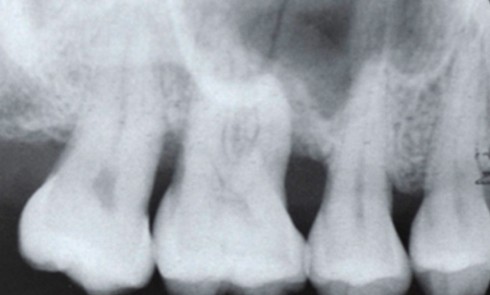

Destruction osseuse induite par la parodontite La dernière classification des maladies parodontales définit la parodontite comme une pathologie inflammatoire chronique multifactorielle associée...